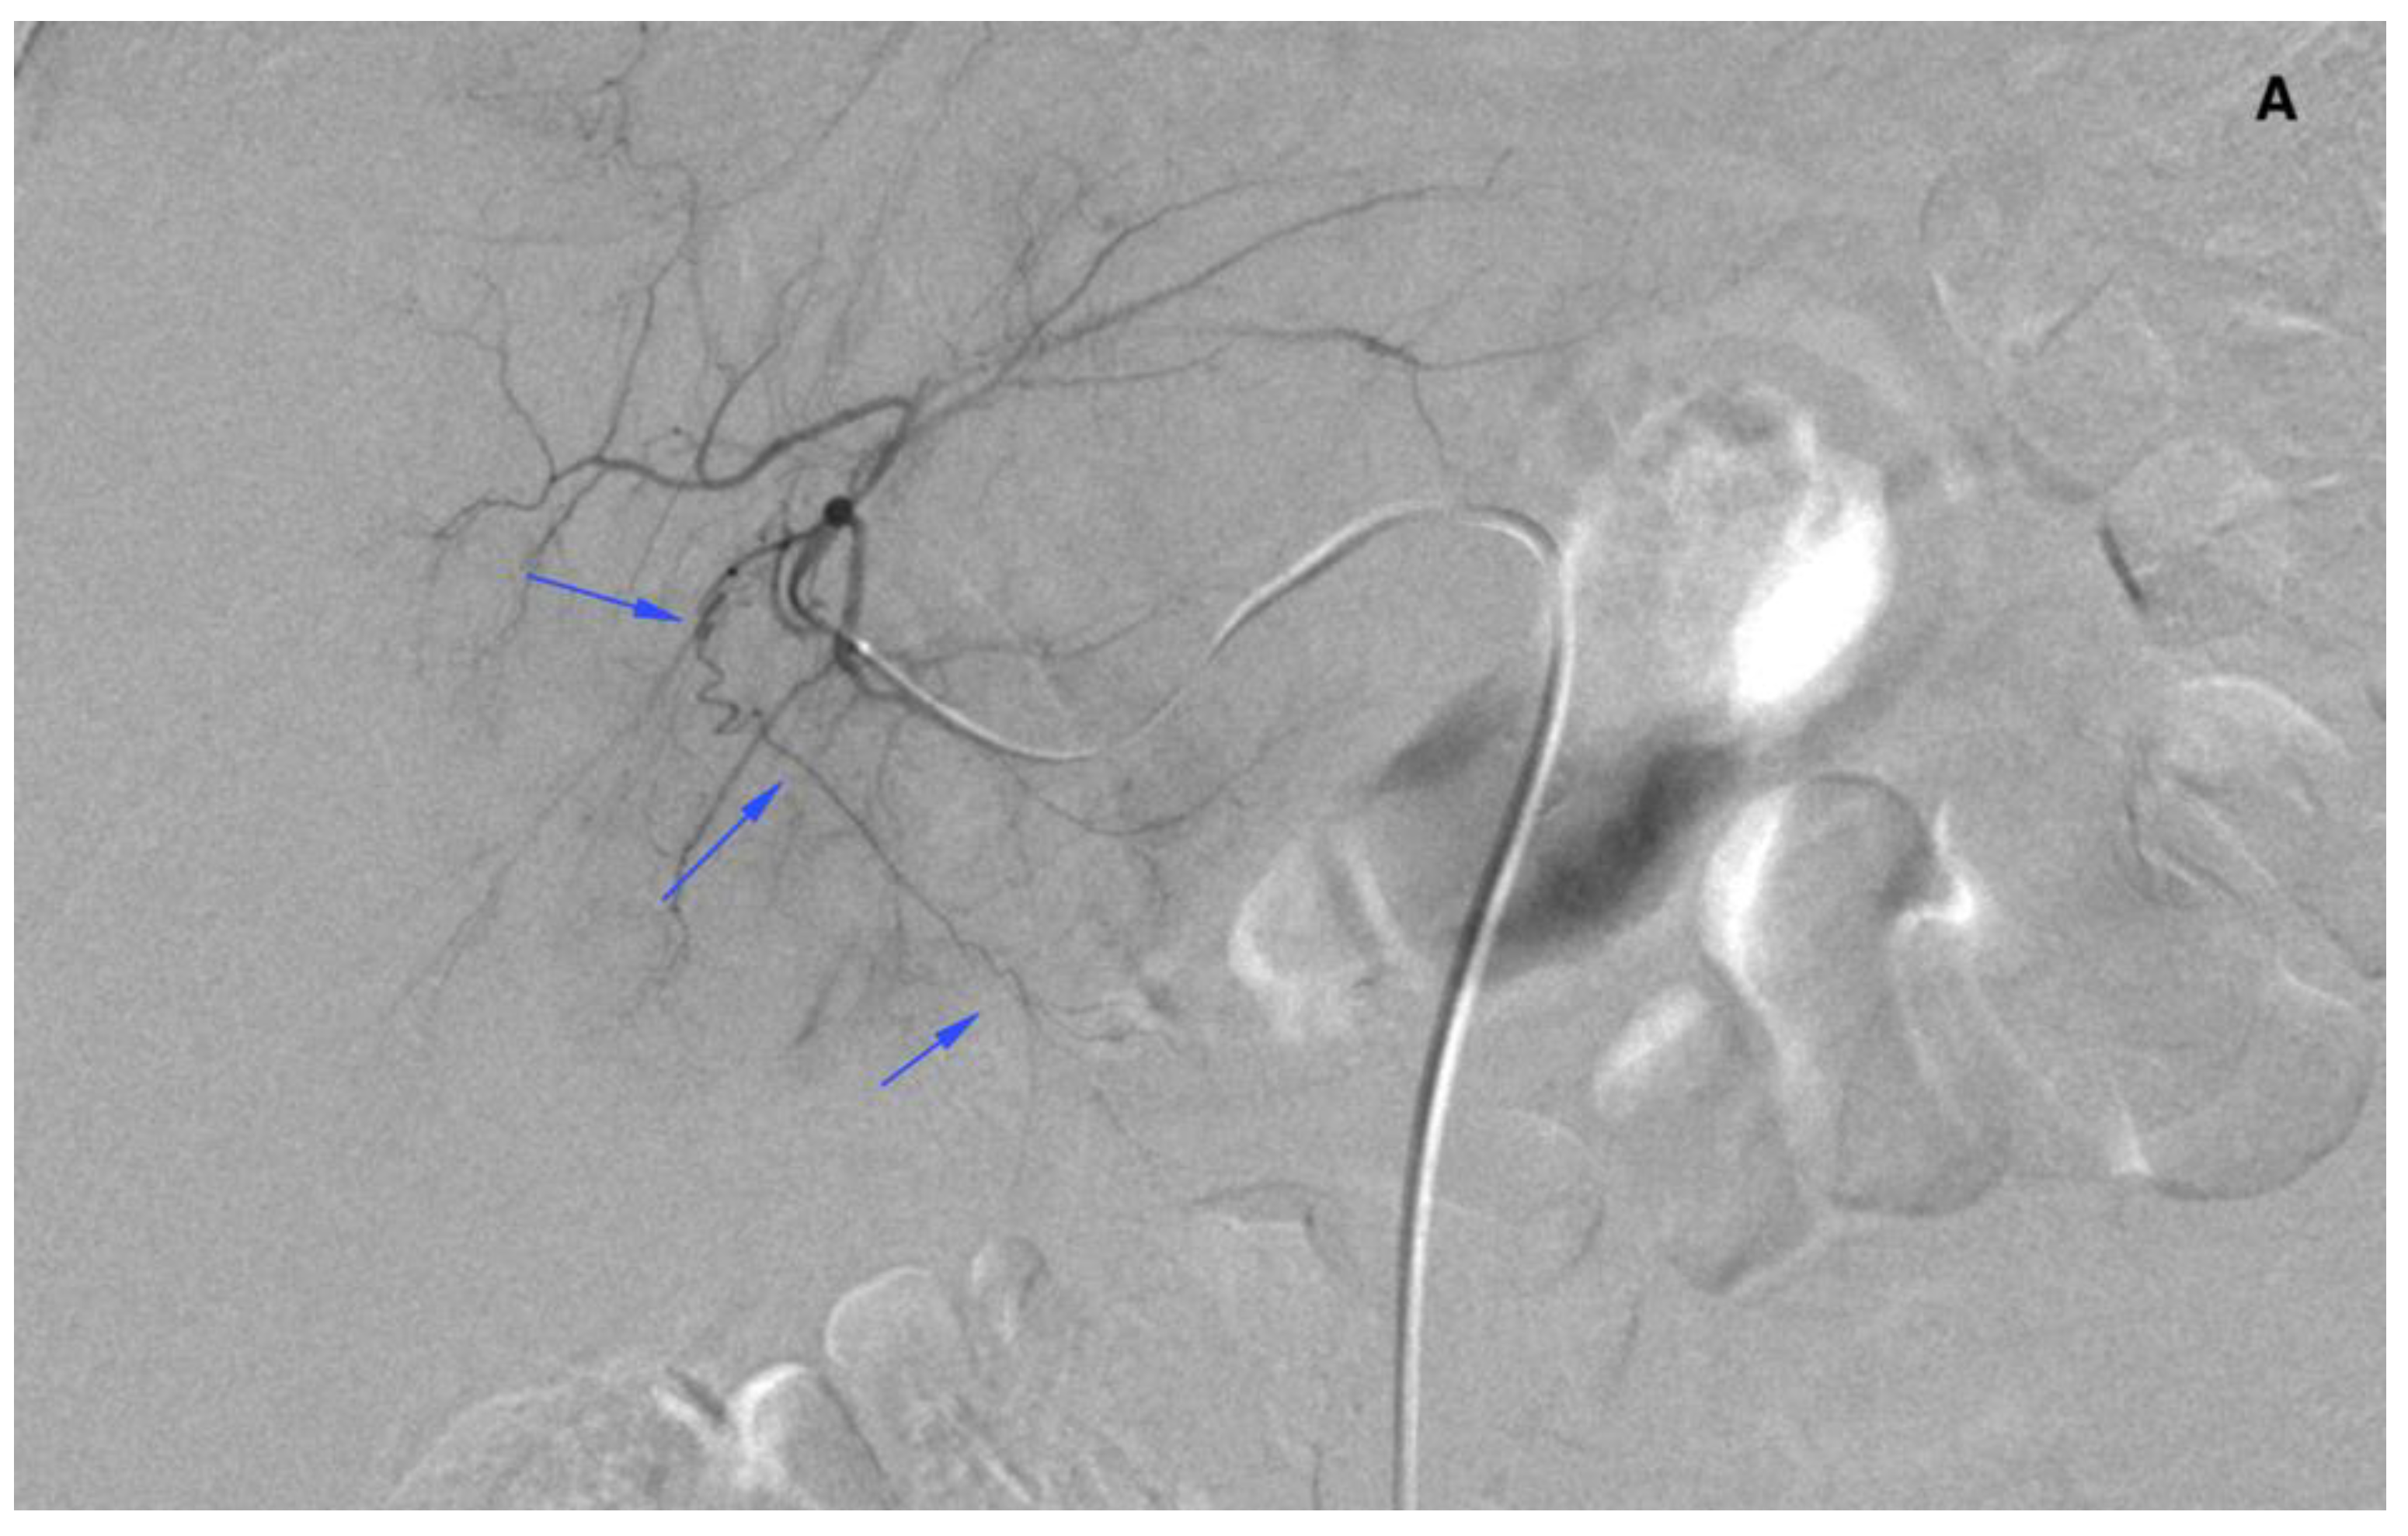

There were two leaks into the gallbladder wall after SIRT administration. Both patients had no signs of cholecystitis or a bilirubin level elevation (Figure 6 and Figure 7). No leaks were noticed in the group of five requalified patients.

Figure 7.

A computed tomography scan depicting asymptomatic cholecystitis (arrows) after the 90Y leak. The patient did not require surgery and was treated conservatively.